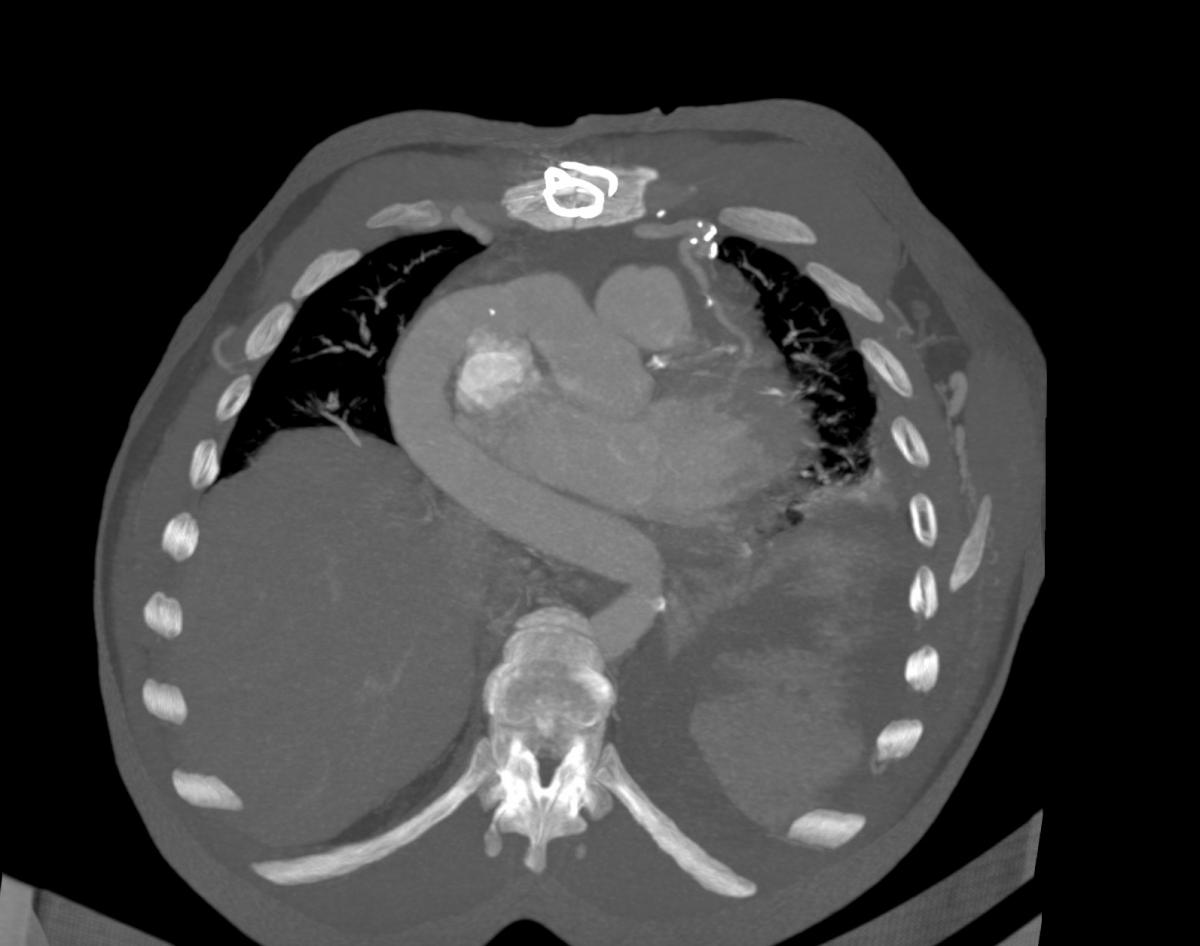

Chest computed tomography (CT) angiography revealed atresia of the aortic arch distal to the origin of the left subclavian artery. The descending thoracic aorta was dilated distal to the occlusion zone and it was supplied by prominent collateral circulation from internal mammary arteries, intercostal arteries, and the vertebrobasilar system (Fig. 2). Cerebral magnetic resonance imaging (MRI) demonstrated diffuse lacunar infarcts with no evidence of berry aneurysms in the circle of Willis.

Figure 8: Postoperative chest CT angiogram 3D reconstruction.